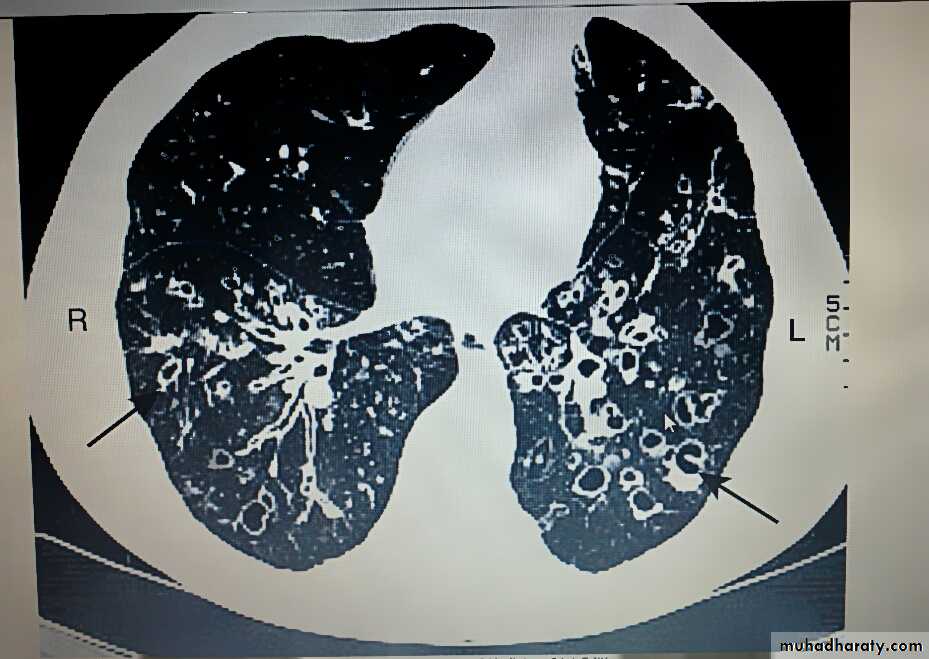

Bronchiectasis

Bronchiectasis means abnormal dilatation of the bronchi.

The bronchiectatic cavities may be lined by granulation tissue, squamous epithelium or normal ciliated epithelium.

Chronic inflammatory and fibrotic changes are usually found in the surrounding lung tissue, resulting in progressive destruction of the normal lung architecture in advanced case